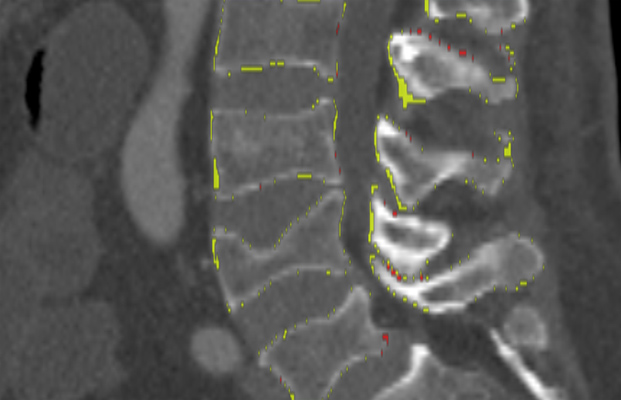

We trained and evaluated the method with five sets of CT and MR scans that visualize the spine. Reference segmentation masks for four of these datasets are publicly available, which allowed for a comparison with other publications that used the same data. Examples of images from the datasets are shown in Figure 3.

The xVertSeg.v1 dataset consists of 15 lumbar spine CT scans of subjects with compression fractures of various grades and types (Ibragimov et al., 2017). Manual reference segmentations are available for the lumbar vertebrae and were defined through a consensus reading of two observers. The scans were reconstructed to in-plane resolutions of and slice thicknesses of . There are currently two other publications that used the same dataset, but with different evaluation/training separation (Janssens et al., 2018; Sekuboyina et al., 2017). We therefore used the scans for evaluation and the remaining 10 scans for training.

Similar performance was achieved for vertebra segmentation in various CT datasets with an average Dice score of and for vertebral body segmentation in an MR dataset with an average Dice score of . Surface distances were lower on CT images compared to MR images ( vs. ), however, there were also fewer training scans available in the MR dataset. Figure 4 illustrates the magnitude of differences of the automatic segmentations from the ground truth segmentations.

In the CT datasets, the segmentation was more accurate on high-resolution dedicated spine scans of healthy subjects compared with low-dose low-resolution chest CT scans and scans of subjects with in some cases severe compression fractures. This is also visible in the segmentation performance stratified by vertebra (Figure 5). Segmentations were more accurate for the lumbar (L1-L5) than for the thoracic vertebrae (T1-T12), which are covered by the more challenging low-dose chest CT scans. Outliers among the lumbar vertebrae correspond to vertebrae from the xVertSeg.v1 dataset, which features a number of severely deformed lumbar vertebrae that are particularly challenging to segment.

In comparison with other vertebra segmentation methods, our iterative instance segmentation approach outperformed previous methods on the thoracolumbar spine CT dataset as well as on the lumbar spine CT dataset. In both cases, there was a substantial improvement in average Dice score and especially also in the surface distance (Table 1). On the xVertSeg.v1 dataset with various fractured vertebrae, our method performed comparable to the method of Sekuboyina et al. (2017) and not as well as the method of Janssens et al. (2018). However, both of these publications used a different separation between training and evaluation data and the results are therefore not directly comparable. For vertebral body segmentation in MR, our approach achieved on average higher Dice scores and lower surface distances than previous methods, but with higher variance compared to Korez et al. (2016). Although the automatic segmentation was overall accurate on low-dose chest CT, the performance was still slightly below the level of interobserver variation (average difference of in Dice score and in surface distance).